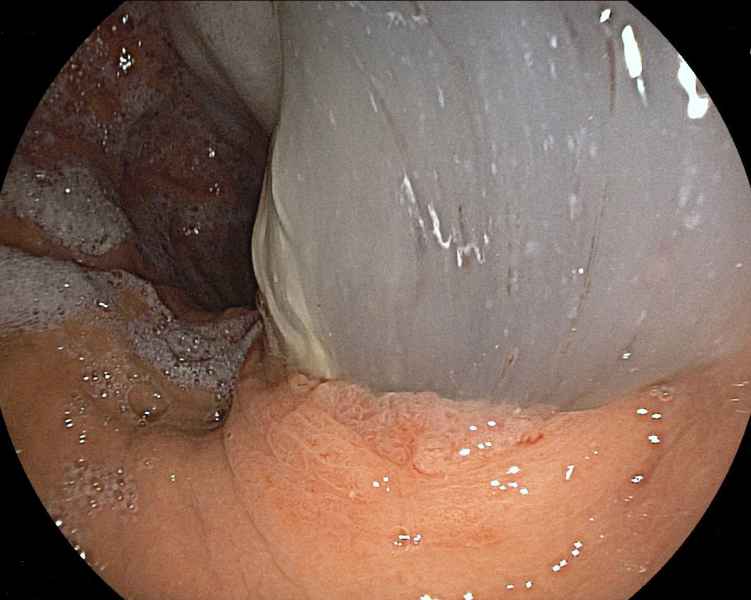

Gastrocolocutaneous Fistula – a rare complication of Percutaneous Endoscopic Gastrostomy

Fotografia